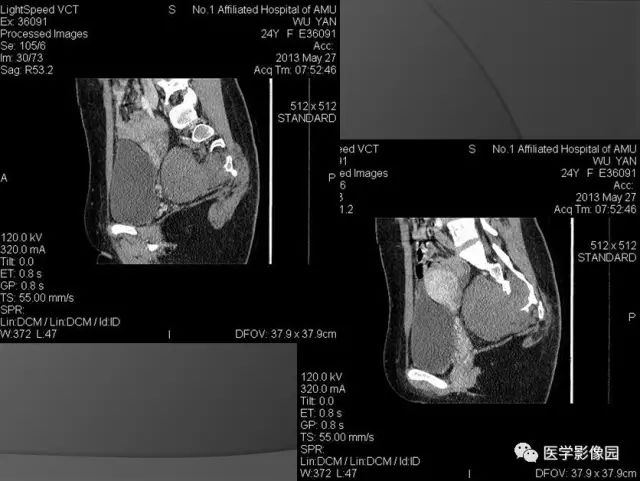

女,35岁,体检发现骶前包块半年余;

查体:肛检:胸膝位12点方向,距肛缘约5cm可触及一质硬包块,上极不可触及,表现光滑,活动度欠佳,退出指套无血染。

影像诊断:子宫后方骶骨前方巨大占位,考虑神经源性肿瘤,神经纤维瘤。

诊断结果:(骶前)节细胞神经纤维瘤